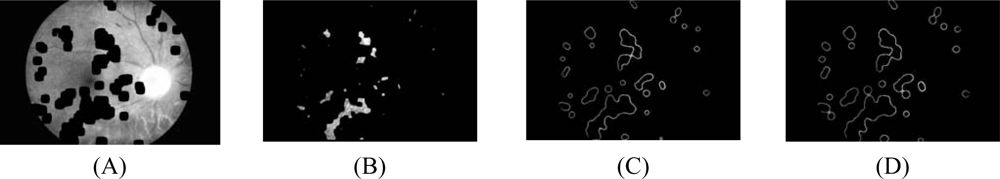

- 4.3 However, some of the resulting edge pixels from the previous step do not represent the edge of the exudates. Some of them are part of vessel’s edge and these vessel edge pixels need to be removed before proceeding to the next step. Quick and approximate blood vessel detection is achieved by using a decorrelation stretch on the Red band. The decorrelation stretching is a process used to enhance or stretch the color differences found in a color image. Contrast exaggeration is used to expand the range of intensities of highly correlated images [24, 25]. Blood vessels can be detected by thresholding this result and the detection result are shown in Fig. 2A.

- The optic disc is quickly detected by using an entropy feature on ICLAHE. The entropy is a statistic measurement of randomness that can be used to characterize the texture of the input image. The optic disc which is normally smooth appears in relatively low intensity in Entropy space. The resulting image is thresholded at an automatically selected grey level, using the Otsu algorithm [26]. Normally, the optic disc can be easily identified as the largest area. However, in some cases, such as the appearance of huge exudates in the image, there might be some areas in the image which are larger than the optic disc. Because the shape of optic disc is round, therefore the optic disc region selection process needs to be made specific to the largest one among the regions whose shapes have compactness, as calculate by Equation 7, close to one. To ensure that all the neighbouring pixels of the thresholded result are also included in the candidate region, a binary dilation operator is also applied. For this step, a flat disc-shaped structuring element with a fixed radius of 11 is used. An example result of an image with all the optic disc area masked out is shown in Figure 2B.

- 4.5 A number of neighboring white pixels of the resulting image from the process 4.1 – 4.4 is counted using a window size of 17 × 17 to form our final feature, namely an image of the number of edge pixels as shown in Figure 3D:where area is the number of pixels in the region and perimeter is the total number of pixels around the boundary of each region.